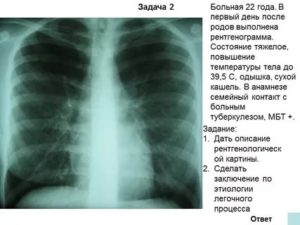

Воспалительные заболевания часто дифференцируют с туберкулёзом лёгких. Туберкулома чаще локализуется на верхушках лёгочных полей. Тень округлая, часто с просветлением в центре — очаг деструкции. Наблюдается расширение корней лёгких.